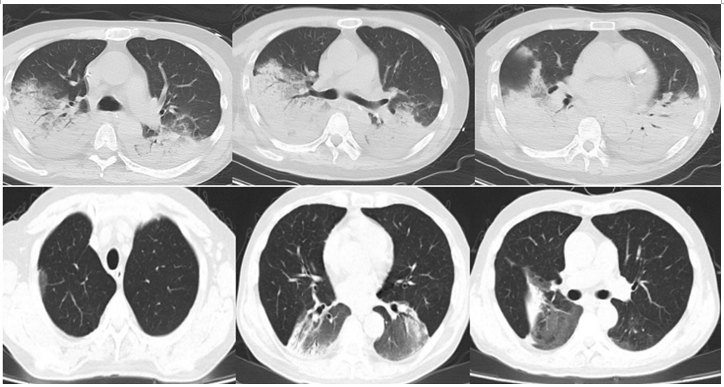

Case 4

患者,女性,63岁,2021年5月27日入呼吸科。主诉:咳嗽、发热1周;热峰40.0℃,“右乳癌术后”3年余,骨转移1年余,1月开始“阿贝西利”化疗,哌拉西林他唑巴坦4.5 g q8h抗感染。因呼吸困难加重于5月30日住RICU。胸部CT提示左肺大片实变。BALF mNGS回报鹦鹉热衣原体(序列数137)。追问病史:家中饲养鹦鹉4只。诊断为鹦鹉热衣原体肺炎,给予美罗培南针→美罗培南针+莫西沙星针→多西环素胶囊(院外)治疗,患者好转。

图片